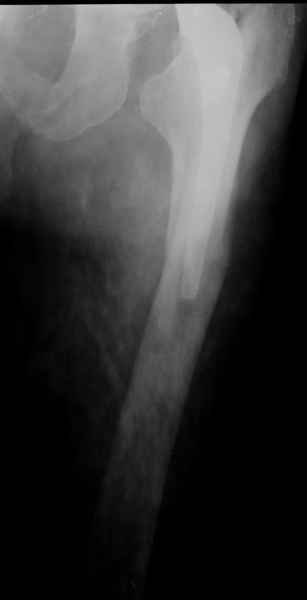

1.Остеосинтез на ножке. Мне кажется, что применительно к этому случаю малоперспективный вариант. Синтез хорош, когда можно его выполнить в малоинвазивном исполнении и достигнуть стабильности. Действительно, если ножка б/цементной фиксации после этого не будет иметь фиксации, то ревизия не будет иметь проблем. В представленном случае стабильность синтеза сомнительная, а проведение доп.иммобилизации приведет к контрактуре суставов.

2. Применение ножки дистальной фиксации, мы отдаем предпочтение ножке Вагнера с фиксацией проксимального отдела на ножке. Более травматичное вмешательство, но при стабильной фиксации ножки реабилитация идет в обычном режиме.

Хочется показать два подобных случая, П-ка З. 72 лет и п-т Г. 80 лет. Сразу принимаю замечание, что это были ножки цементной фиксации, просто под руками не было бесцементника.